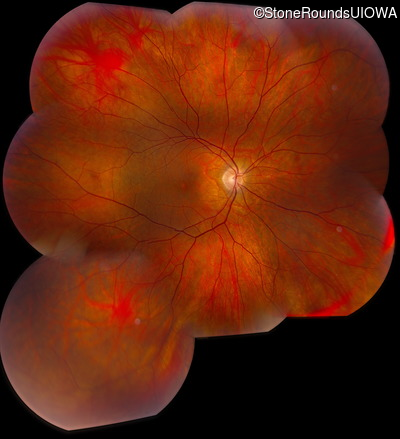

Fundus Montage - Right - 20/40

Exemplar

Fundus Montage - Left - 20/25